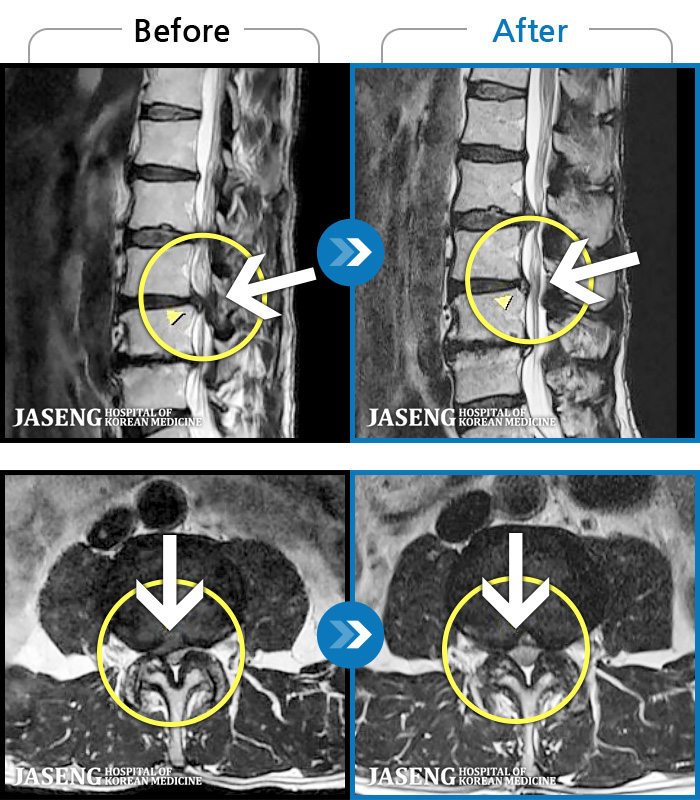

MRI ġ

96 MRI ũ ʸ Ȯϼ.

㸮 ߹ٴڱ ,

ǿ

ȯ

㸮ũ

[_㸮ũ] ð ɰų, Ͼ ݺ ߳ Į ° ־ϴ.

No.96

ȸ 34

2026.03.13